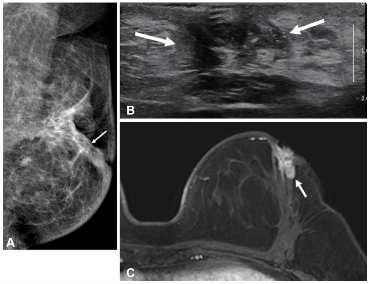

[Image] Imaging findings in a young breast cancer patient with ipsilateral in-breast recurrence after surgery. Postoperative breast imaging obtained 2 years after surgery in a patient aged 50 years or younger who did not undergo preoperative MRI, demonstrating ipsilateral in-breast recurrence: (A) mammography, (B) ultrasonography, and (C) MRI.